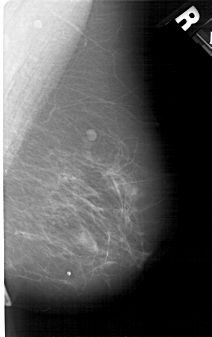

A_1278_1.RIGHT_MLO

RIGHT_MLO LINES 5041 PIXELS_PER_LINE 3166 BITS_PER_PIXEL 12 RESOLUTION 43.5 NON_OVERLAY